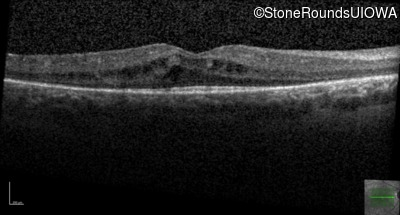

Age at visit: 7 years

This 7 year old girl has had very poor vision in dim light and slightly subnormal acuity her entire life.

Age at visit: 7 years (Visit 2)

Age at visit: 8 years

Age at visit: 9 years

Age at visit: 10 years

Age at visit: 12 years

Age at visit: 13 years

Age at visit: 14 years

Age at visit: 15 years

Age at visit: 16 years

Age at visit: 17 years

Age at visit: 19 years

Age at visit: 21 years